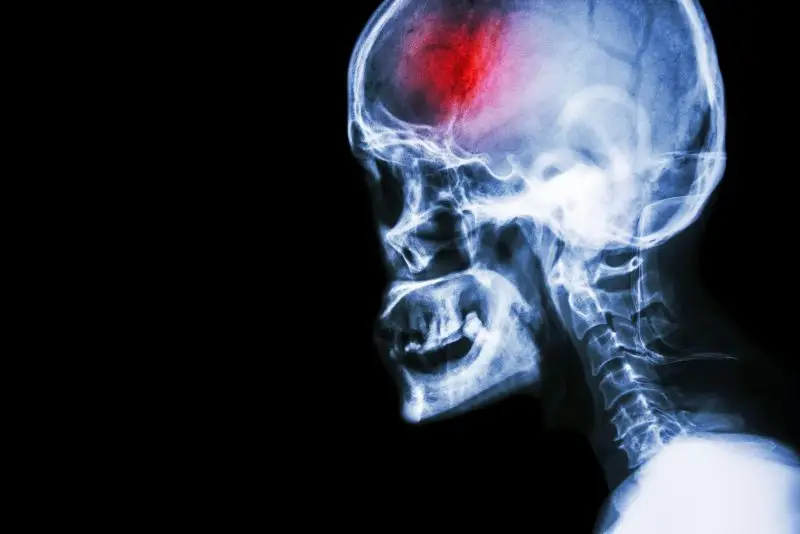

A stroke (previously known as a cerebrovascular accident) when there is a decreased flow of blood to the brain from either a blockage in the blood vessels that supply the brain (ischemic stroke), or a bleed from the blood vessels that supply the brain (hemorrhagic stroke). When the blood flow to the brain is blocked it prevents the brain from getting the needed oxygen and nutrients to function. Without oxygen the brain cells can be permanently damaged or die and the physical and mental functions related to that area of the brain will be affected. A stroke is a medical emergency and rapid treatment is crucial to decreasing the damage caused by a stroke.

Types Of Strokes

There are three types of strokes:

- Ischemic stroke: a stroke that is caused by a blockage (clot) that disturbs the blood flow to the brain.

- Hemorrhagic stroke: a stroke that is caused by a bleed that disturbs the blood flow to the brain and puts pressure on the surrounding tissue.

- Transient ischemic attack: often referred to as a “mini-stroke” or TIA, where the blood flow to the brain is temporarily disturbed and as a result causes temporary signs and symptoms of a stroke that resolve quickly .